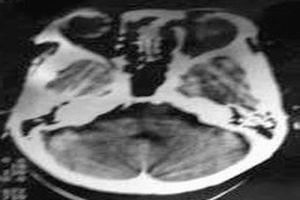

2.CT及MRI檢查CT檢查費用雖較X線照片高,但其密度分辨高於X線、對病骨內的囊變、破壞、鈣化和骨化顯示較X平片敏感準確。CT橫斷面克服了常規X平片前後重疊的缺點,可用於頭顱、脊柱和骨盆等重疊較多的部位。MRI對MAS的病理顯示無疑較常規X線或CT更敏感,能顯示大部分在X線平片或CT片上不能顯示的病灶(如壞死、液化、出血),纖維或纖維骨樣組織病灶在T1加權像和T2加權像均呈低信號。骨幹結構不良在病變的不同階段可有不同的病理改變。如病灶內的壞死液化在T1加權像上呈低信號,在T2加權像上呈高信號。如壞死組織合併出血,T1加權像上呈高信號。病灶內的鈣化和周緣的硬化在T1加權像和T2加權像上呈明顯的低信號。此外,少數病灶邊緣在T1和T2加權像上呈薄帶狀環狀高信號,其病理機制不清。某些病灶在T1加權像上呈不均勻的中低信號,而在T2加權像上則平片所見的“絲瓜筋”樣纖維結構不良。而液化的病灶在T1加僅像上為中低信號,在T2加權像上為均勻高信號。